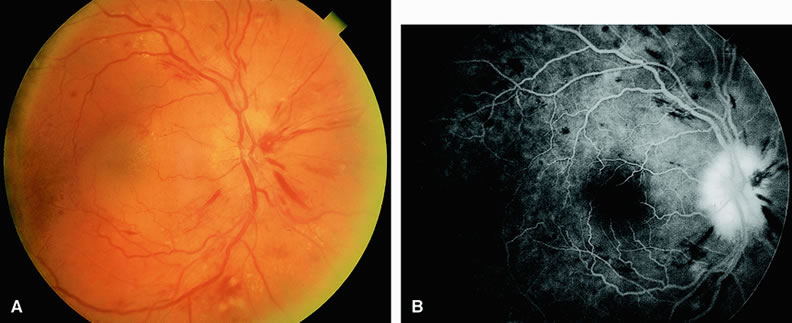

CENTRAL RETINAL VEIN OBSTRUCTION In eyes with central retinal vein obstruction, a thrombus is usually found in the obstructed vessel at or near the lamina cribrosa. Ophthalmoscopic signs of retinal vein obstruction include dilated tortuous veins, intraretinal hemorrhage, and ischemic retinal edema.10 Cotton-wool spots and a swollen optic disc are also often seen. Other less common signs of central retinal vein obstruction include vitreous hemorrhage and exudative retinal detachment. Several classifications have been employed to define central retinal vein obstructions. Central retinal vein obstructions can be divided into ischemic and nonischemic variants, depending in part on whether large areas of retinal capillary nonperfusion are present or absent. This classification is clinically useful because data from the Central Retinal Vein Occlusion Study Group11 and others12 suggest that laser panretinal photocoagulation can result in a regression of neovascularization of the iris, thereby preventing neovascular glaucoma. Compared with eyes that have the ischemic type, eyes with nonischemic central retinal vein obstruction typically have a visual acuity of 20/200 or better, relatively few cotton-wool spots, and less marked retinal hemorrhage.13 Fluorescein angiography usually shows an increased retinal arteriovenous transit time secondary to delayed retinal venous filling. Delayed retinal arterial filling can also be present. The retinal capillary bed is generally well perfused (Fig. 10). The retinal veins appear as a hypofluorescent silhouette against the bright choroid. There is also variable staining of the retinal veins and variable leakage on the angiogram. Approximately 20% of nonischemic central retinal vein occlusions will progress to ischemic central retinal vein occlusions. Ischemic central retinal vein obstructions generally reduce a patient's visual acuity to 20/200 or worse, most commonly to the counting-fingers or hand-motions range. Numerous cotton-wool spots and severe four-quadrant retinal hemorrhaging are often seen. Fluorescein angiography reveals confluent regions of retinal capillary nonperfusion (Fig. 11). Views of the posterior pole, as well as those of the four quadrants, may be necessary to demonstrate the capillary dropout. Magargal and associates12 quantitated the amount of retinal capillary nonperfusion in a posterior-pole 30-degree view in eyes with central retinal vein obstruction and calculated an ischemic index (area of retinal capillary nonperfusion/total area within the posterior 30-degree view). They found that when the index was 80% or greater, approximately 45% of eyes eventually developed rubeosis iridis and neovascular glaucoma. In some eyes with central retinal vein occlusion, determining the degree of retinal capillary nonperfusion with fluorescein angiography is difficult. Worsening visual acuity and progressive intraretinal bleeding indicate that an eye may be progressing toward a more ischemic state.14 In eyes with central retinal vein obstruction and a visual acuity of 20/200 or worse, performing fluorescein angiography at the initial visit can be useful to evaluate perfusion of the retinal capillary bed. The presence of a large amount of intraretinal blood in the posterior pole is not necessarily a contraindication to performing the study, particularly because these eyes are probably more prone to ischemia. The retinal blood generally diminishes rapidly anterior to the posterior pole, facilitating angiographic evaluation of the peripheral retina. BRANCH RETINAL VEIN OBSTRUCTION Branch retinal vein obstruction usually occurs at the intersection of a branch retinal artery with a vein. In general, the artery overlies the vein, and the two vessels share a common adventitial sheath at the crossing. Retinal hemorrhages are present along with cotton-wool spots (Figs. 12 and 13). These hemorrhages usually are reabsorbed over a period of months. Numerous microvascular abnormalities generally remain, and macular edema may be persistent. The Branch Retinal Vein Occlusion Study Group15 demonstrated that eyes with branch retinal vein obstruction and a visual acuity of 20/40 or worse may benefit from grid laser therapy to reduce macular edema. This study group recommended waiting at least 3 months after the onset of the obstruction to permit clearing of the retinal blood before performing fluorescein angiography. If the study shows that macular edema is responsible for the visual loss, grid laser therapy to the affected region within the vascular arcades can be considered. In cases in which foveal nonperfusion is responsible for the decrease in vision, laser therapy has not been shown to improve vision. Eyes with branch retinal vein obstruction and retinal capillary nonperfusion can develop neovascularization of the retina and/or disc. New vessels on the retina or optic disc intensely leak fluorescein dye, whereas larger collateral vessels on the optic disc or in the retina usually do not; thus, fluorescein angiography is helpful in differentiating between neovascularization and collateral vessels. Proper identification of posterior-segment neovascularization in eyes with branch retinal vein obstruction is important because scatter laser treatment in such cases has been shown to reduce vitreous hemorrhage in these eyes.16 In addition, fluorescein angiography can be used to identify the areas of retinal capillary nonperfusion requiring therapy. Scatter sector laser photocoagulation should be delayed until the onset of retinal neovascularization. |